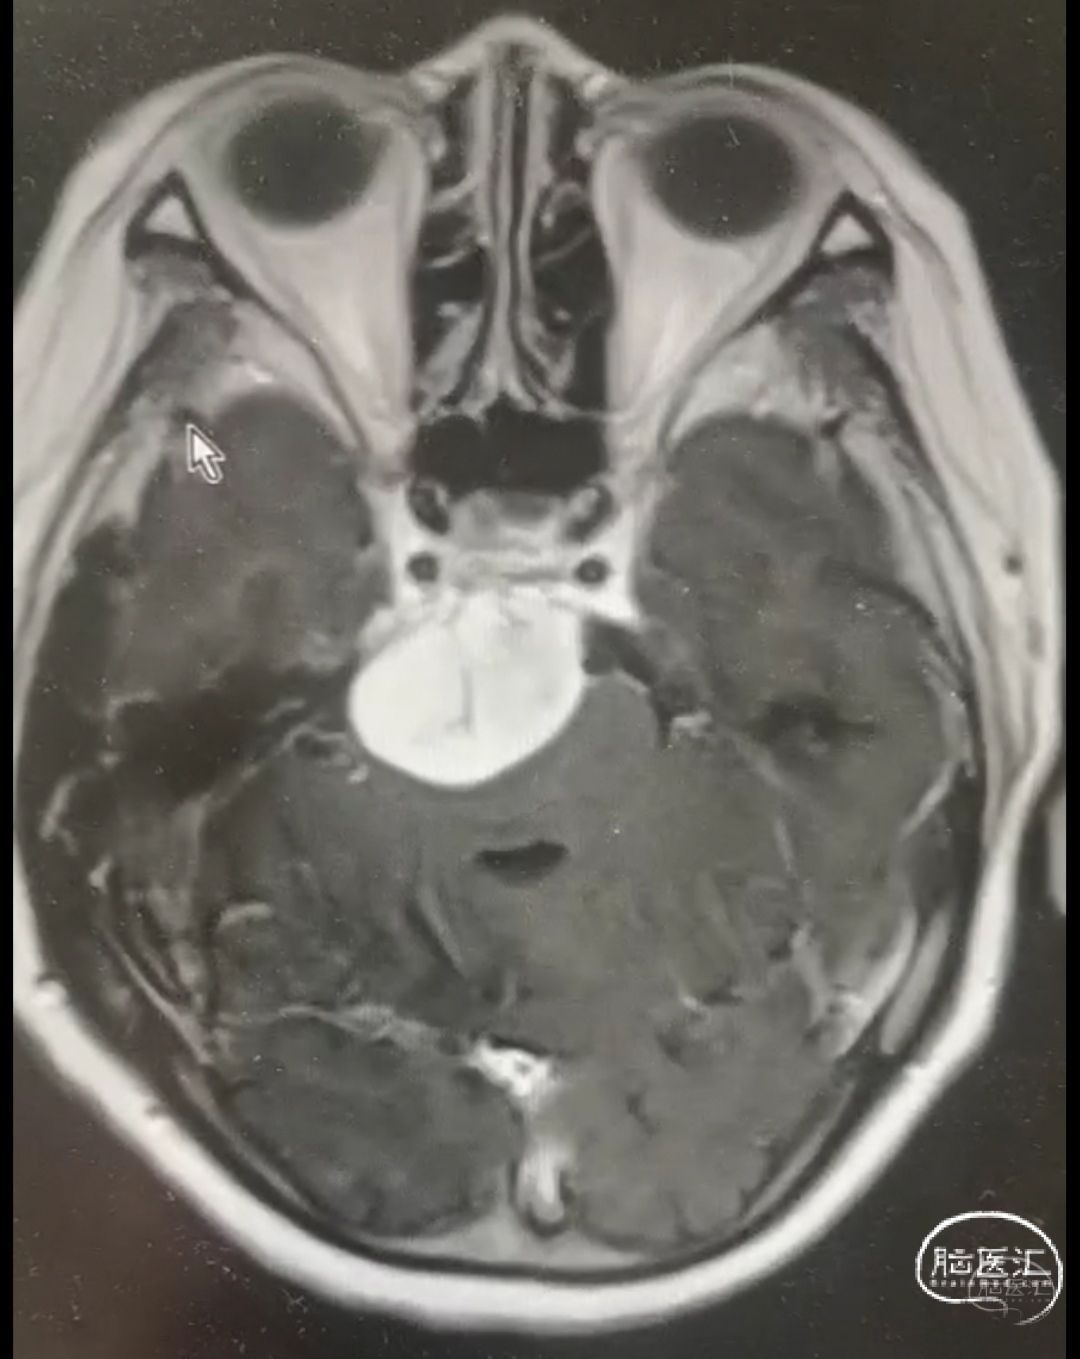

患者男性,51岁;

主诉:头晕2月,间断复视1月;

查体:神志清楚,右侧外下方复视;

辅助检查:头颅MRI增强影像诊断:右环池占位,神经鞘瘤可能,请结合临床及MRI平扫原片。